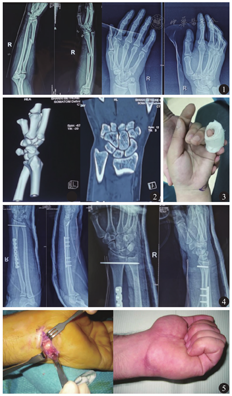

患者 男,24岁。因摔伤致右腕关节及右前臂疼痛肿胀伴活动受限2 d就诊。患者系驾驶摩托车时向前方摔倒,右前臂及右手背侧着地。临床检查:右腕及前臂肿胀、疼痛、畸形及功能障碍,可及明显反常活动及骨擦感,右手末梢色泽、皮温及感觉与健侧无明显差别,右手第五掌骨基底部及右腕关节尺侧疼痛、压痛明显,可触及一骨性突起,并可推动;伴有右手握力的减退。右腕关节及右尺桡骨X线正侧位片示:右侧桡骨骨折合并桡尺远侧关节脱位,右腕豌豆骨脱位可能(图1)。腕关节CT检查示:右腕豌豆骨掌侧脱位合并右手第五掌骨基底部骨折(图2)。麻醉前先行体外标记右腕关节尺侧痛点,并透视证实为豌豆骨(图3)。臂丛神经阻滞麻醉下先行右侧桡骨骨折切开复位钢板内固定术,再行右侧桡尺远侧关节分离闭合复位克氏针内固定术,固定后术中C臂机透视满意。再屈曲腕关节并于前臂旋前位向尺侧推移复位豌豆骨,C臂机透视复位满意。于手腕轻微弯曲及前臂旋前位,采用超过掌指关节及肘关节的石膏固定(图4)。术后1个月门诊复查,腕关节功良好,右腕尺侧疼痛消失。2个月后拆除石膏并拔除桡尺远侧关节克氏针,腕关节屈伸及旋转功能均良好,握力正常。

急性豌豆骨脱位可以行手法闭合复位和石膏外固定,治疗效果良好,包括良好的腕关节功能和接近正常的握力,并能减少尺神经损害的发生。对于早期存在尺神经症状的患者,需要立即行手法复位和固定。闭合复位不成功者应行切开复位或切除治疗。手术切口的选择,大多数研究描述了一种纵向切口技术,但亦有研究者使用了沿鱼际的横向切口(图5),具有良好的美观效果[9]。